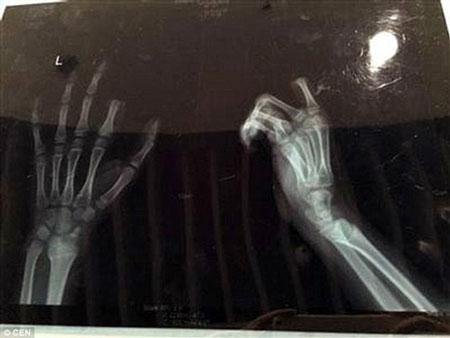

Do được đưa vào viện kịp thời, sau 3 giờ phẫu thuật, các bác sỹ tại bệnh viện ở Tô Châu đã nối tạm thời ngón trỏ bị đứt lìa cho cậu bé. Tuy ca phẫu thuật thành công nhưng rất có thể ngón tay trỏ của Peng không thể cử động tốt như trước.

Tuy ca phẫu thuật thành công nhưng rất có thể ngón tay trỏ của Peng không thể cử động tốt như trước.

Bác sỹ Zhou Rong, một trong những người trực tiếp phẫu thuật cho Peng cho biết: "Hiện ngón tay đã được kết nối tạm thời nhưng chúng tôi vẫn phải theo dõi thêm. Nếu cậu bé cử động quá nhiều sẽ gây ra tình trạng nghẽn mạch dẫn đến việc ngón tay có nguy cơ hoại tử hoàn toàn".